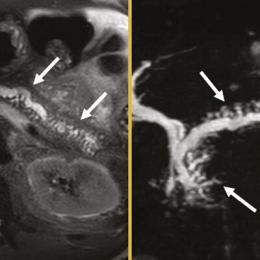

Ictus amnésique

Une femme âgée de 48 ans est vue en consultation pour un épisode d’amnésie régressive d’installation rapide (quelques...